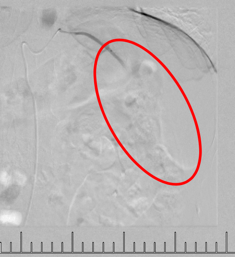

灌注藥物及栓塞后“烏云”消失

肋間動(dòng)脈阻斷營(yíng)養(yǎng)來(lái)源